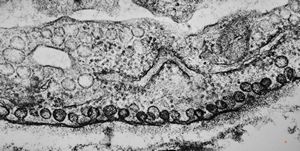

mouse heart atrium … granules of the natriuretic peptide